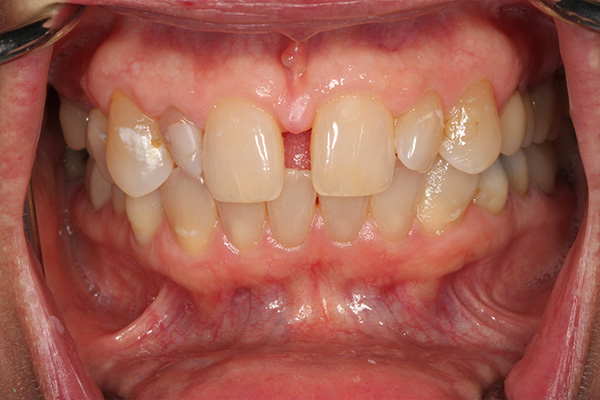

After dealing with years of erosion and stains, this patient came to us to learn more about how to improve her smile. With dental crowns, we were able to restore her teeth with a natural, white and confident smile. We understand that sometimes life prevents us from making our way to the dentist, but this patient was pleased to learn that it's never too late to receive the dental care you need and deserve.